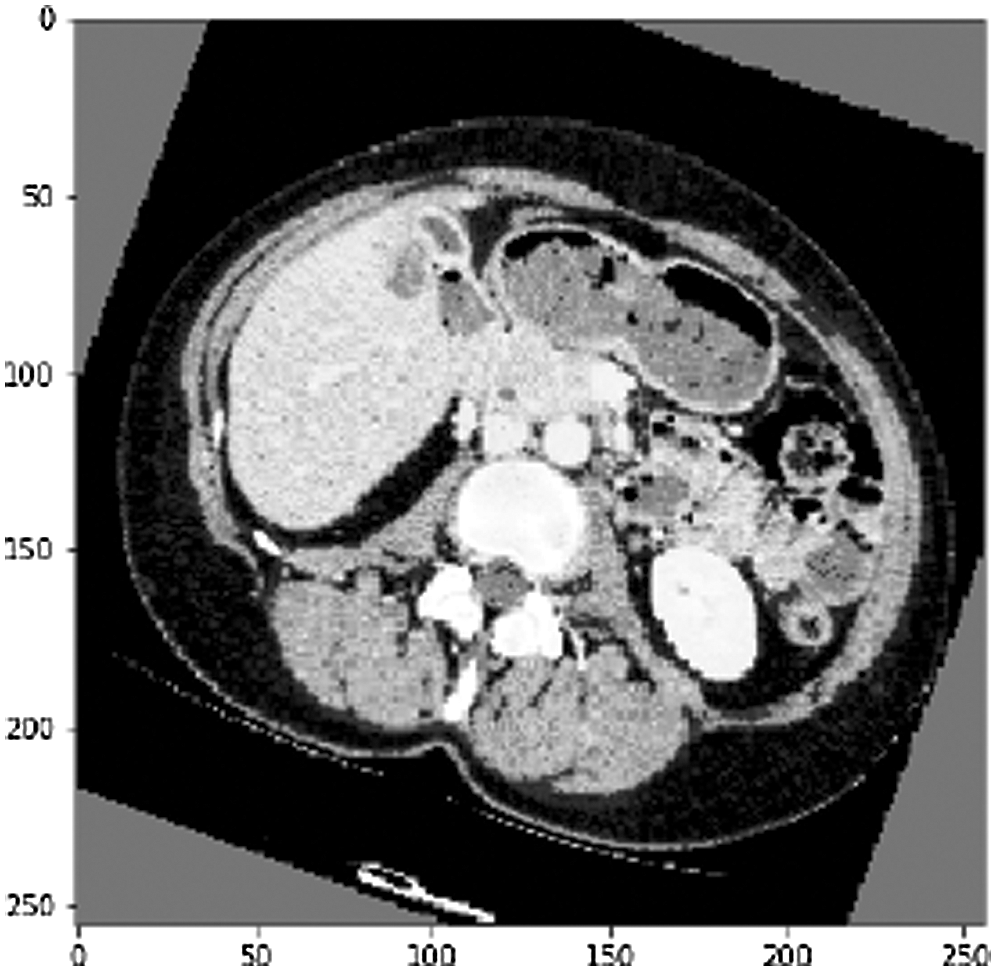

One of the irregular examples (see Fig. 8). accomplished an Accuracy of 99.4% and a True Value Accuracy of 98.1%. We can see the Confusion Matrix (see Fig. 9).

Figure 8: CT slice of the first random sample before liver segmentation

Consequence of liver segmentation on the first irregular cut (see Fig. 8). True mark on the left and anticipated on the right, white is pixels with liver and dark are pixels with no liver. Confusion matrix (see Fig. 8) from the predicted value of the first slide.